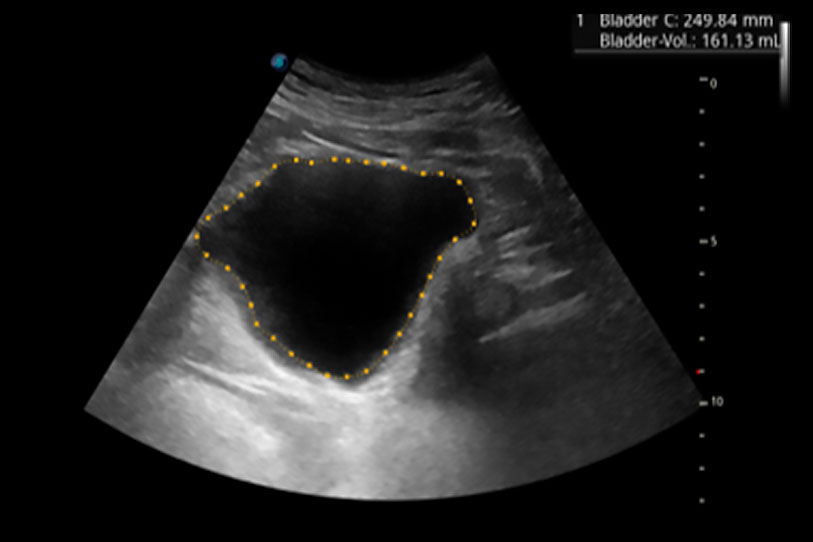

一鍵自動(dòng)識(shí)別膀胱壁及自動(dòng)測(cè)量膀胱容積,不受膀胱形狀和大小的限制,幫助醫(yī)生快速精準(zhǔn)獲得測(cè)量的數(shù)據(jù)。